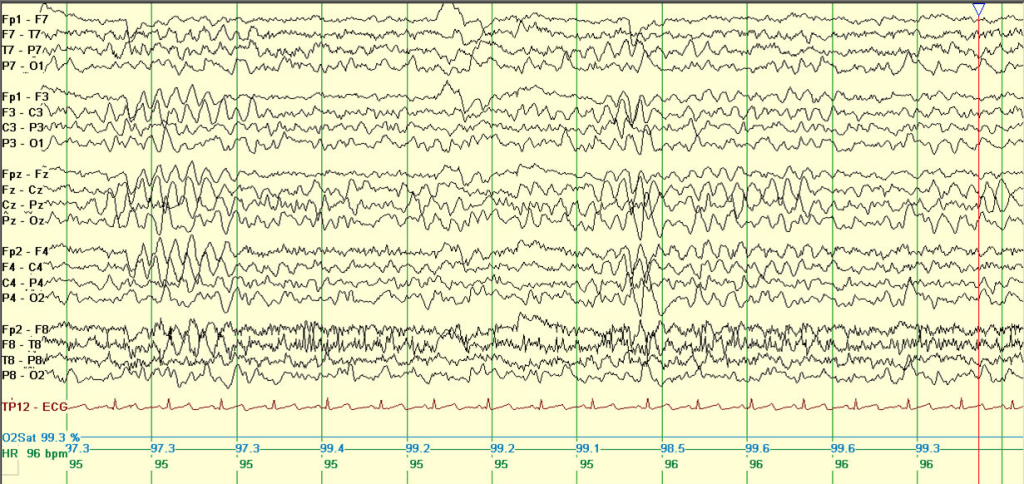

Epilepsy with myoclonic-atonic seizures (EMAtS) is diagnosed based on a combination of clinical presentation and electroencephalogram (EEG) findings. While individuals with EMAtS may experience a variety of seizure types, the presence of myoclonic-atonic seizures is a defining feature of the condition. Most children with EMAtS show typical development before the onset of seizures, though some may have mild developmental delays. The condition usually begins early, with 94% of cases presenting before the age of five. Around 60% of affected children also experience generalized tonic-clonic seizures.

Diagnostic imaging such as MRI and blood tests typically appear normal in EMAtS cases. EEGs often reveal characteristic abnormal brain wave patterns, such as “spike and wave” or “polyspike and wave,” although early EEGs may sometimes appear normal. Genetic testing can support the diagnosis, particularly when variants in the SLC2A1 gene are identified. This gene is linked to glucose transport in the brain, and mutations can cause a deficiency in GLUT1 transporters. Since certain SLC2A1 variants respond well to specific treatments, including dietary interventions, genetic sequencing can play a crucial role in guiding management. In some cases, a lumbar puncture may be used to detect low glucose levels in the spinal fluid, further supporting a diagnosis linked to GLUT1 deficiency.